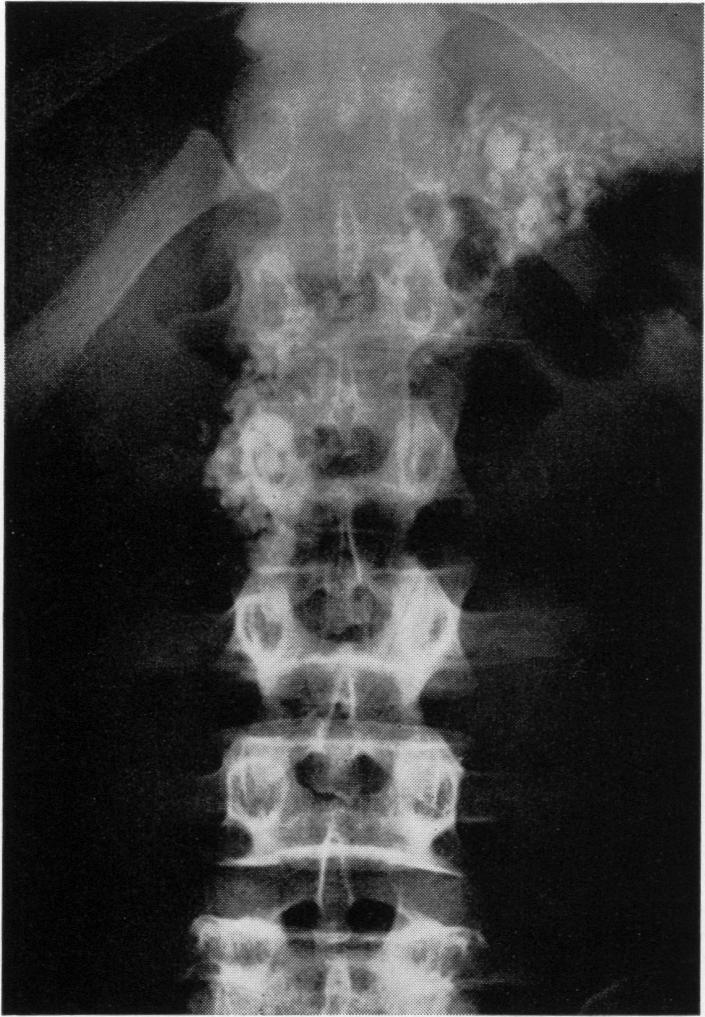

Chronic relapsing pancreatitis; treatment by subtotal gastrectomy and vagotomy.

Ann Surg. 1950 Feb;131(2):145-58, illust. doi: 10.1097/00000658-195002000-00002.